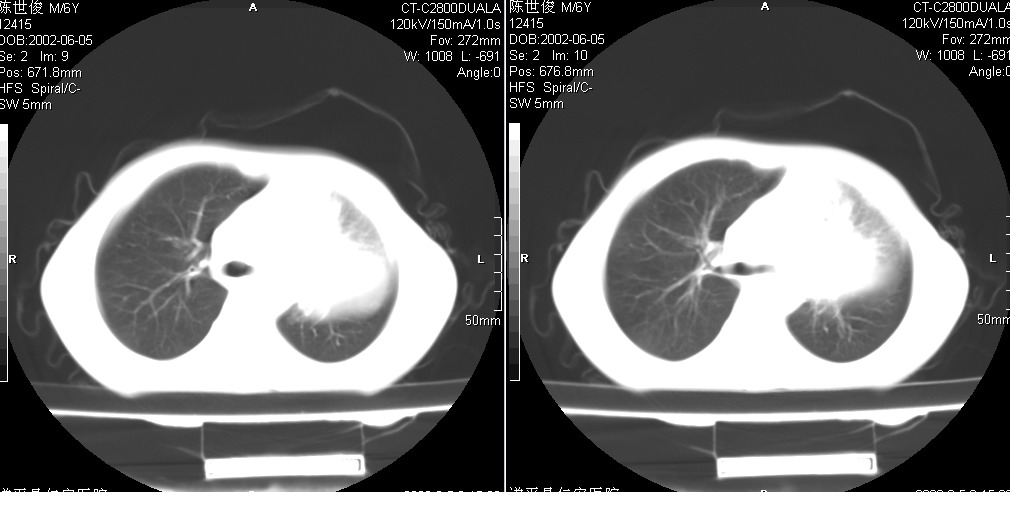

以下是引用xxhwh在2008-6-10 18:40:00的发言:[br]男,6岁,无规则发热一月余,体温在37.8——39度之间。一月前拍胸片示左上肺密度增高影,进行抗炎治疗8天,复查胸片未明显吸收。又改变抗菌素继续治疗半月,照胸片示病灶吸收不明显,行ct检查[br]征象:左上肺前段呈密实影,内可见支气管气像,远侧见絮状模糊影,中上纵隔左移。[br]意见:左上肺前段膨胀不全及感染,考虑为支气管异物或支气管内膜结核所致,[br]建议追问有无异物吸入史,行痰检及ppd检查